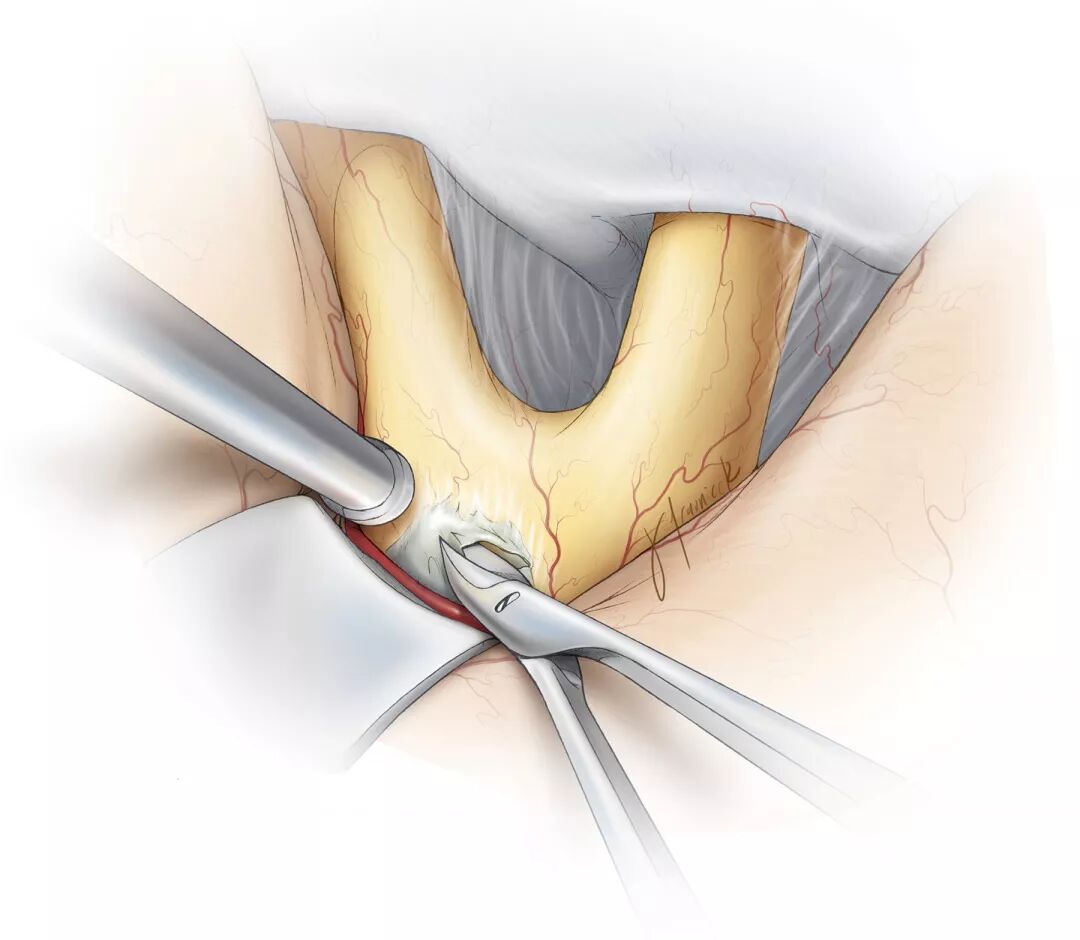

图4:要显露终板并经其操作,必须适度牵拉额叶。终板被肿瘤侵犯后,其颜色与视交叉相比,明显变得浅灰。在切开终板时,必须仔细保护视交叉,在视交叉上充分细致解剖,辨清终板的确切边界。

![]()

图5:经左侧眶颧开颅显露终板(术前相关图像见图1),浅灰色的肿瘤致终板扩大。已标记出前交通动脉复合体,要避免过度牵拉血管结构。读者可体会手术通道的狭窄。